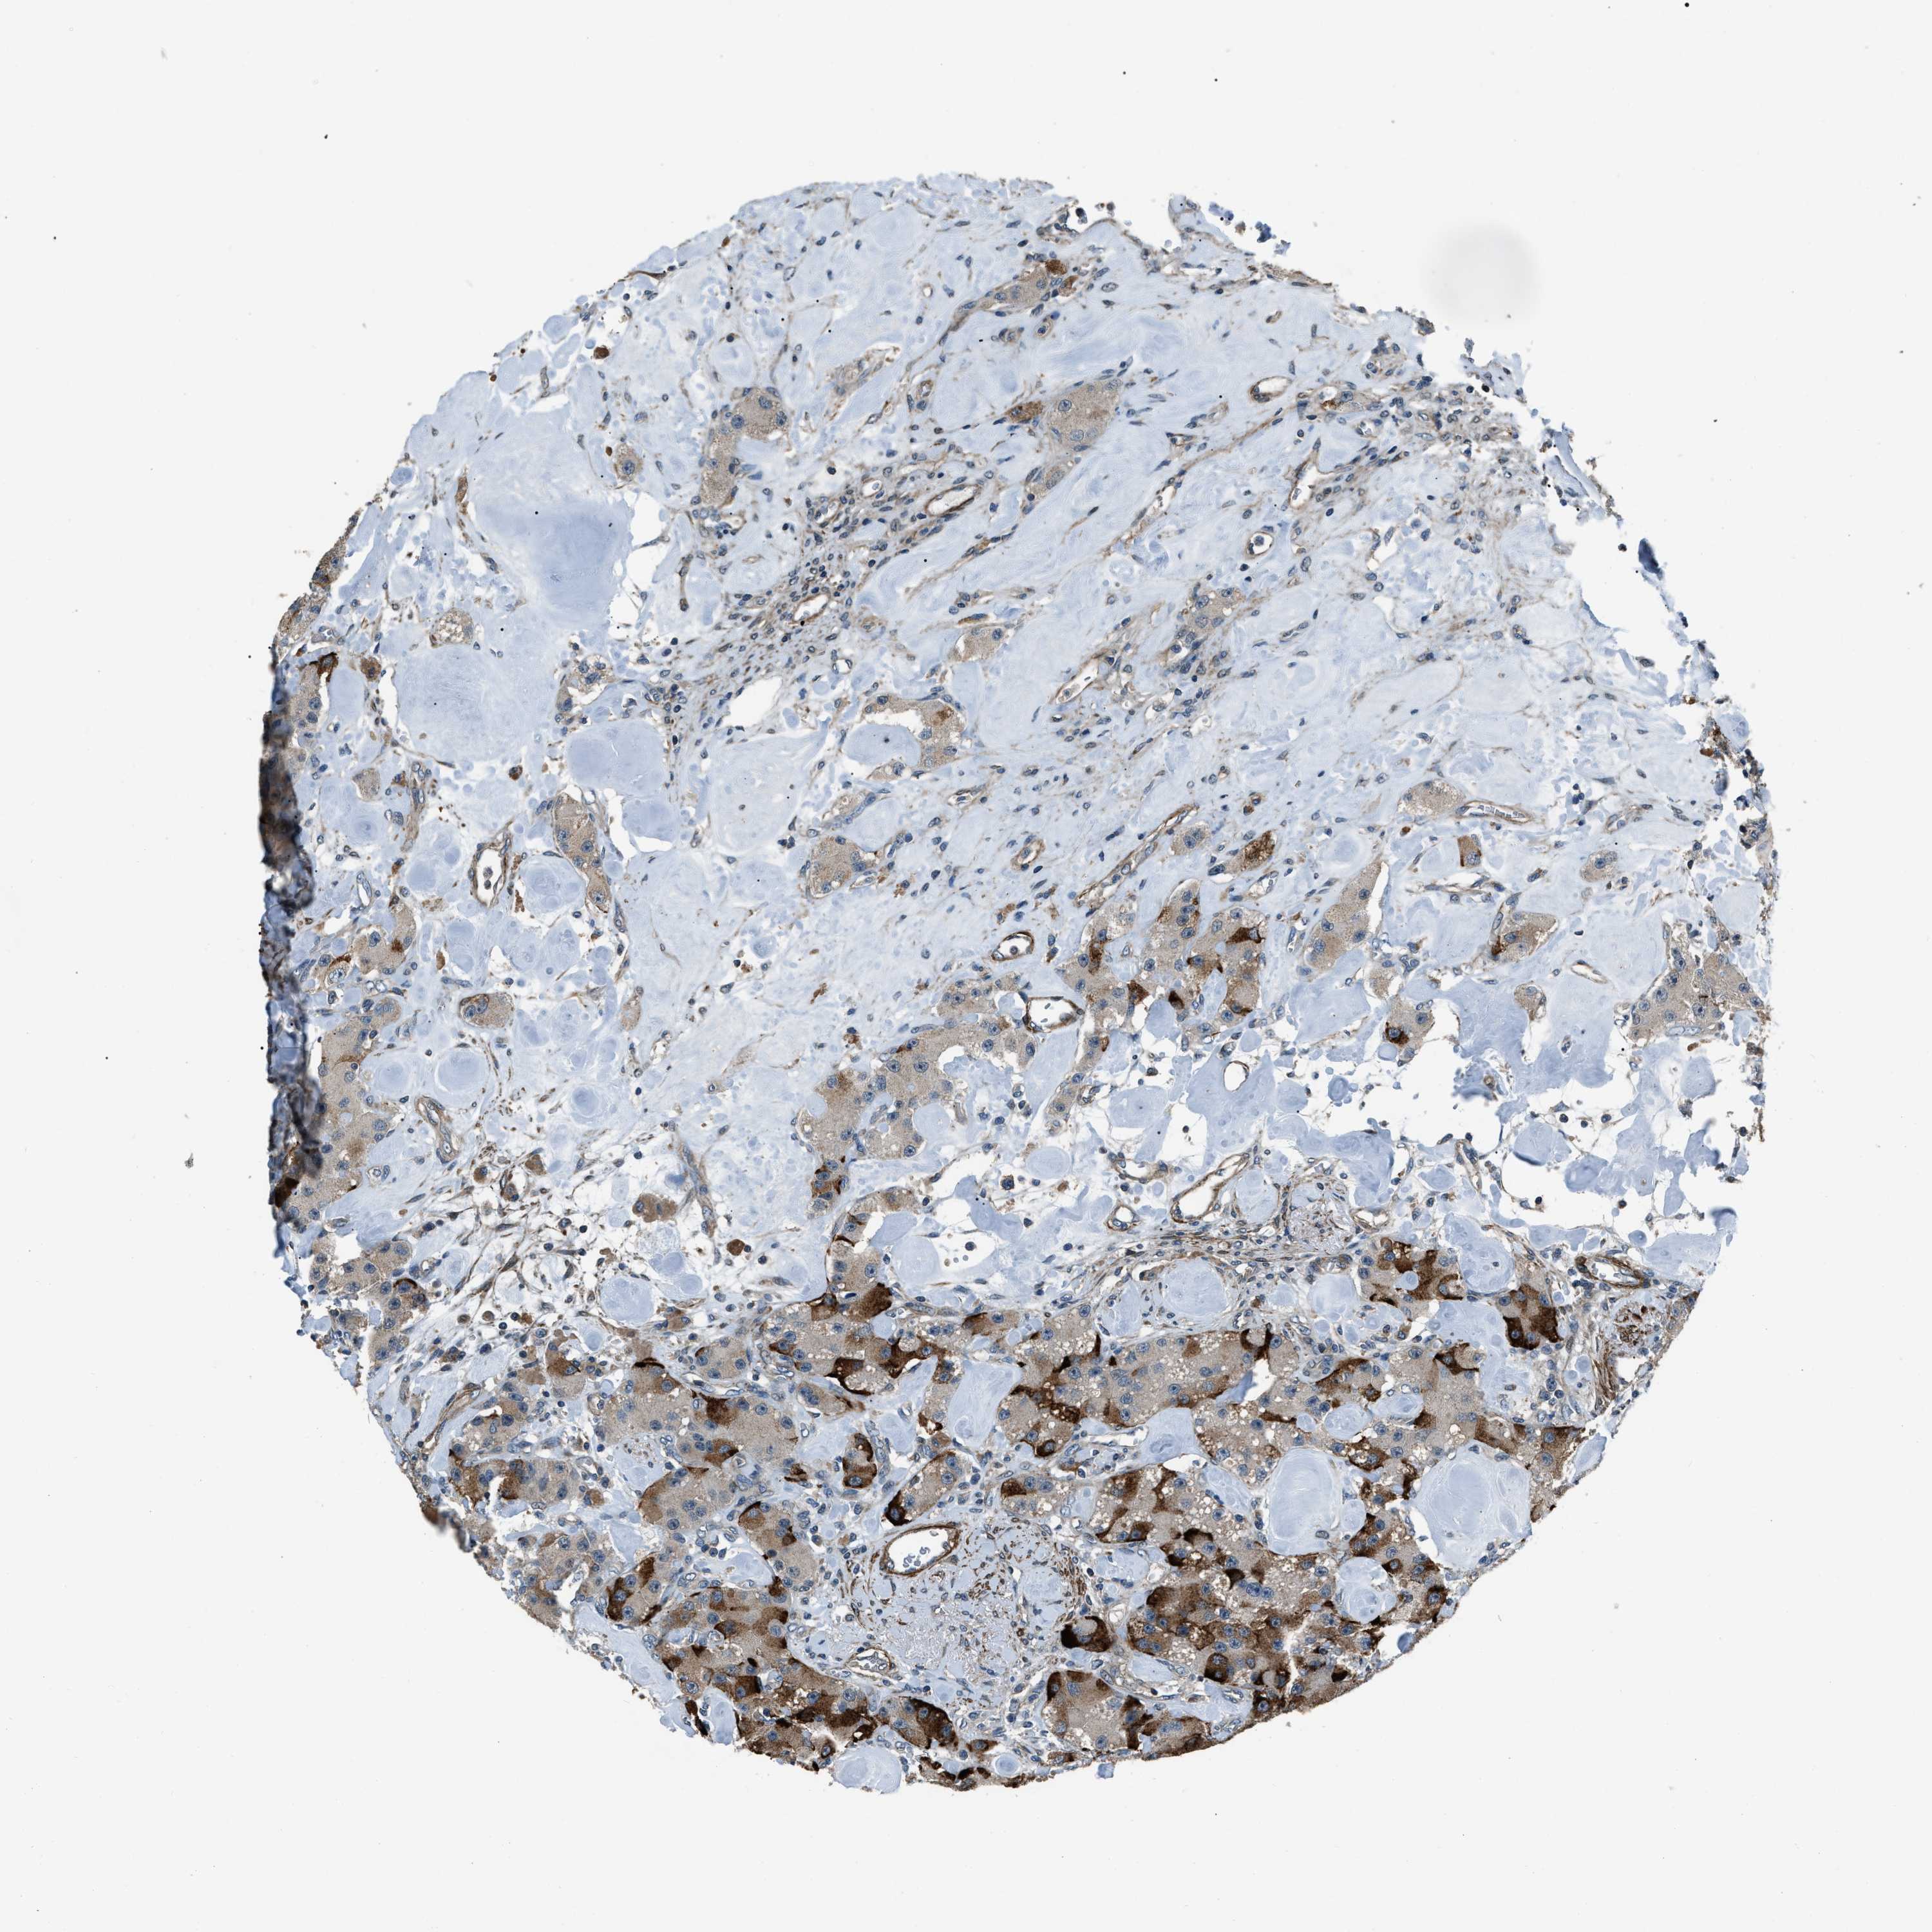

CARCINOID - Protein expressioni

A mouse-over function shows sample information and annotation data. Click on an image to view it in a full screen mode. Samples can be filtered based on level of antibody staining by selecting one or several of the following categories: high, medium, low and not detected. The assay and annotation is described here.

Antibody staining in the annotated cell types in the current human tissue is reported as not detected, low, medium, or high, based on conventional immunohistochemistry profiling in selected tissues. This score is based on the combination of the staining intensity and fraction of stained cells.

Each image is clickable and will lead to virtual microscopy that enables deeper exploration of all samples and also displays staining intensity scores, fraction scores and subcellular localization as well as patient and tissue information for each sample.

Antibody HPA019136

Staining

High

Medium

Low

Not detected

Intensity

Strong

Moderate

Weak

Negative

Quantity

>75%

75%-25%

<25%

None

Location

Nuclear

Cytoplasmic/membranous

Cytoplasmic/membranous,nuclear

Carcinoid, malignant, NOS